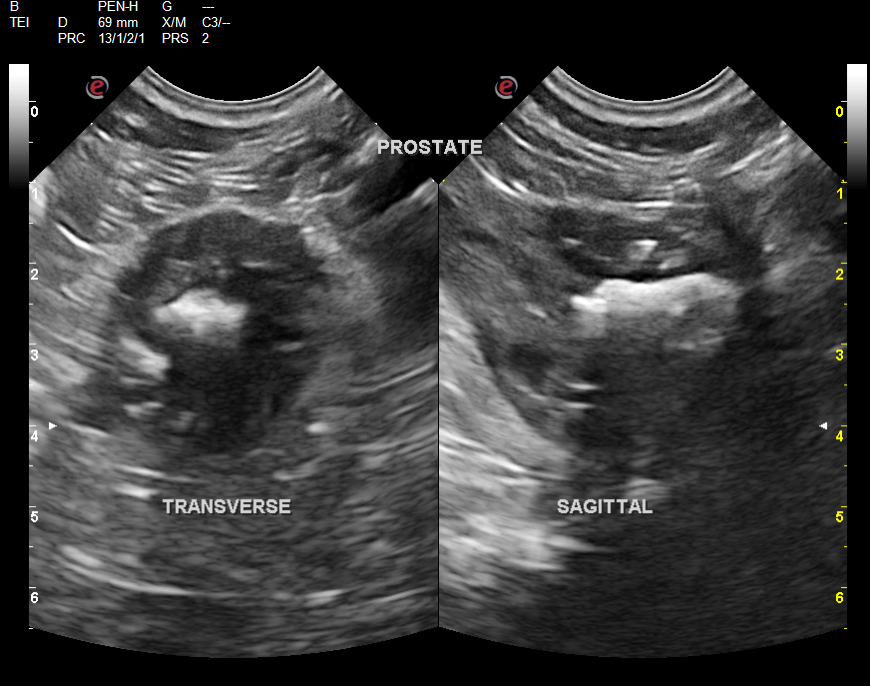

A 9-year-old neutered male Cocker Spaniel dog with a history of chronic diarrhea was presented for evaluation of recent onset hematuria. Prostatomegaly was present on rectal palpation. On survey radiographs, uroliths and narrowing of the distal colon at the pelvic inlet were evident.